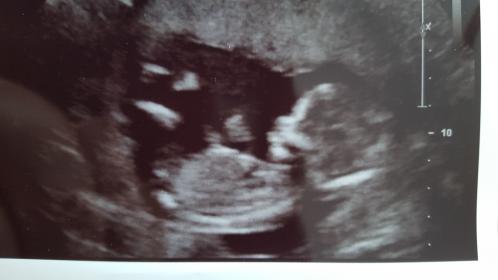

This is from My 14 week scan and the tech didnt want to

Talk about the gender of the baby.

İ really want it to be a girl so i Hope You can help me with the guessing 😊😊

Tricky, I don't think the nub is properly visible in these pics. Do you have more, or a video or a potty shot?

That last pic *might* be showing a girly nub, but I really don't want to give you too much hope. You could post the other pics if you have any more, you never know if there is a better nub shot among them.